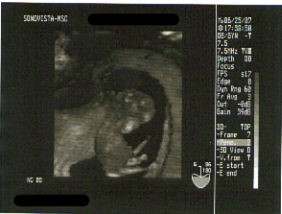

今回は3Dの映像も見せて貰えましたよ。

今まで何となくしか分からなかった形がちゃんと見えた!

脚がピョコっと出てる~。

すごーい。

※上が頭です。